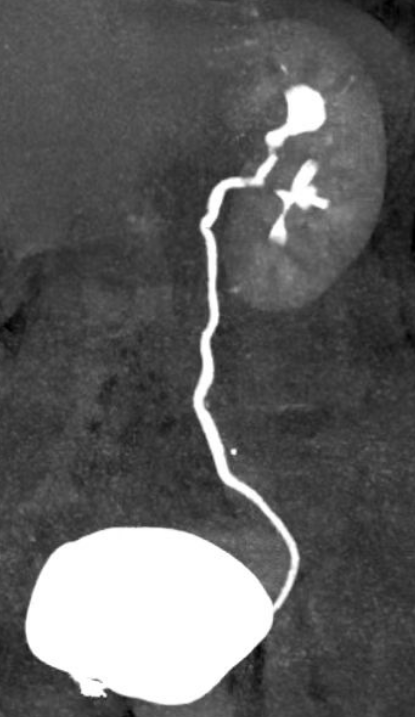

近日,我院泌尿外科团队成功为一位饱受多年右侧腰腹部疼痛困扰的67岁患者(化名:李阿姨),实施了高难度、高精度的腹腔镜下右肾切除术。手术过程顺利,患者恢复良好,术后第4天即康复出院。 李阿姨长期遭受右侧腰腹部的疼痛困扰。来院就诊后,泌尿外科蒋勇军主任详细询问病史得知,她曾因右侧肾结石接受过手术治疗。进一步的系统检查(包括下腹部CT平扫和CT尿路成像)揭示了问题根源:患者右侧肾脏存在严重肾积水,肾实质已极度萎缩、变薄,功能完全丧失。影像学显示,在排泄期长时间观察下,右肾已无显影,确认其功能完全丧失。 蒋主任分析认为,患者既往的结石病史可能导致输尿管狭窄或闭锁,引发了长期的尿路梗阻和肾积水,最终造成右肾不可逆的萎缩。而萎缩肾脏可能存在的炎症,正是其持续疼痛的原因。 面对患者切除无功能病肾的诉求,蒋勇军主任团队经过严谨评估,决定迎难而上,采用腹腔镜微创技术实施右肾切除术。该手术属于最高难度的四级手术,对医院综合实力和主刀医生的技术要求极高。手术面临两大挑战: 1、组织粘连重:萎缩的肾脏因继发炎症,与周围组织形成致密粘连,分离难度大。 2、血管处理难:萎缩肾脏的血管结构不清、纤细且被纤维组织包裹,解剖分离需极其精准,稍有不慎易损伤邻近重要血管和器官。 6月17日,手术如期进行。术中腹腔镜视野下,可见患者右肾萎缩呈“皮囊样”,肾实质薄如纸片,与周围组织粘连紧密,肾血管结构不清。蒋勇军主任团队凭借丰富的腹腔镜操作经验和精湛的解剖技巧,如同精雕细琢般,仔细分离粘连组织,精准处理纤细的肾血管及输尿管,最终完整、安全地切除了病变右肾。手术历时约3小时,顺利完成。 术后病理检查结果证实为“肾萎缩”,与术前诊断完全一致。在泌尿外科医护团队的精心治疗和护理下,李阿姨恢复迅速,疼痛解除,术后第4天即满意出院。出院前,蒋主任特别叮嘱她:务必保护好唯一的左肾,定期复查泌尿系统,发现异常及时就医处理。